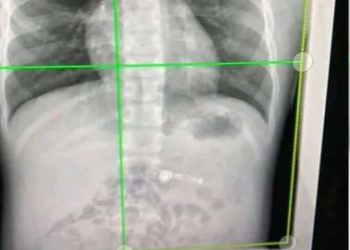

Moradabad (Uttar Pradesh): A man died after his friend pumped air into his rectum with an air compressor. The incident ...

Read moreDetailsMoradabad (Uttar Pradesh): A man died after his friend pumped air into his rectum with an air compressor. The incident ...